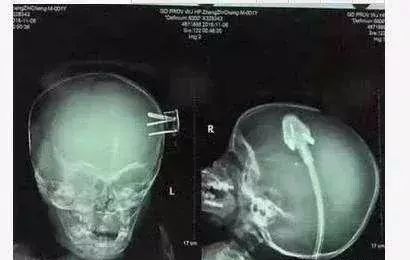

2岁孩子滑倒摔下了床,谁知床边地上一个三孔插头三根金属插销直接刺入了孩子的颅内,家人吓坏了,不敢贸然动插头,便赶紧把孩子送到医院了。

好在孩子比较幸运,插头没有损伤大血管,而家长也没有拔插头造成二次伤害,医生说如果插头的位置再稍微错一点,后果不堪设想。